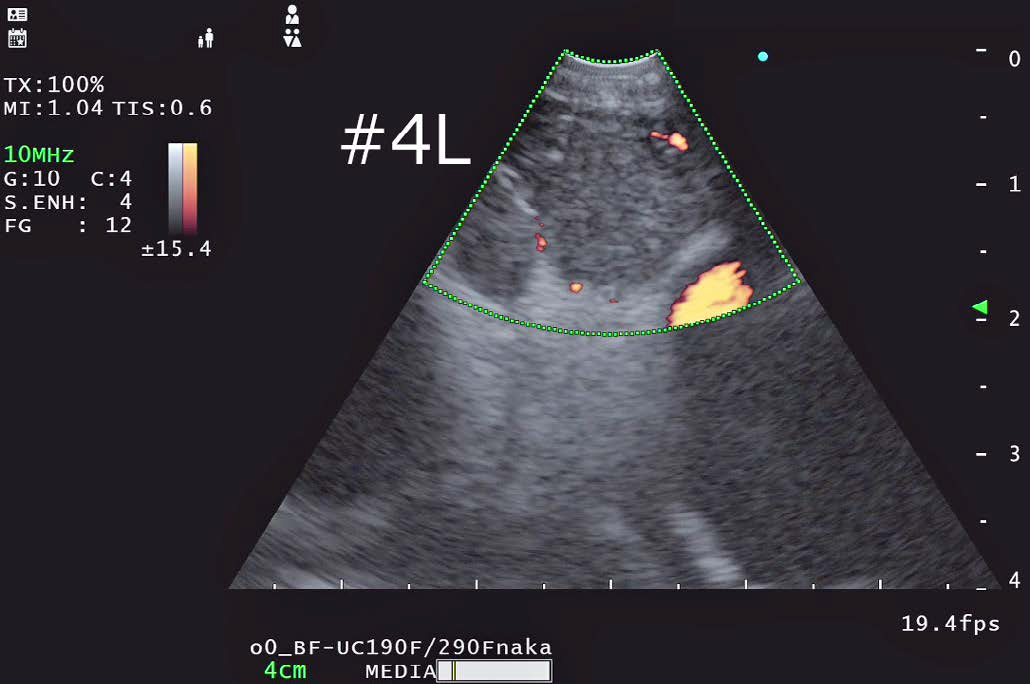

• 4L リンパ節観察

FLOW モード

•  EU-ME2と同様に右記のドプラーモードが使用可能である。

基本となるBモードの解像度が向上している影響か、色のにじみが少なくメリハリの利いたドップラー画像になっていると感じた。

当院ではTBNA施行時には血管からのはみ出しを抑えて血流表示するハイフローを基本的に使用し、穿刺前に血管介在を確認している。

• カラーフロー:血流の向きと速度をカラー表示

• パワーフロー:血流の強度をカラー表示

• ハイフロー:血流の向きと強度をカラー表示

• カラーフロー